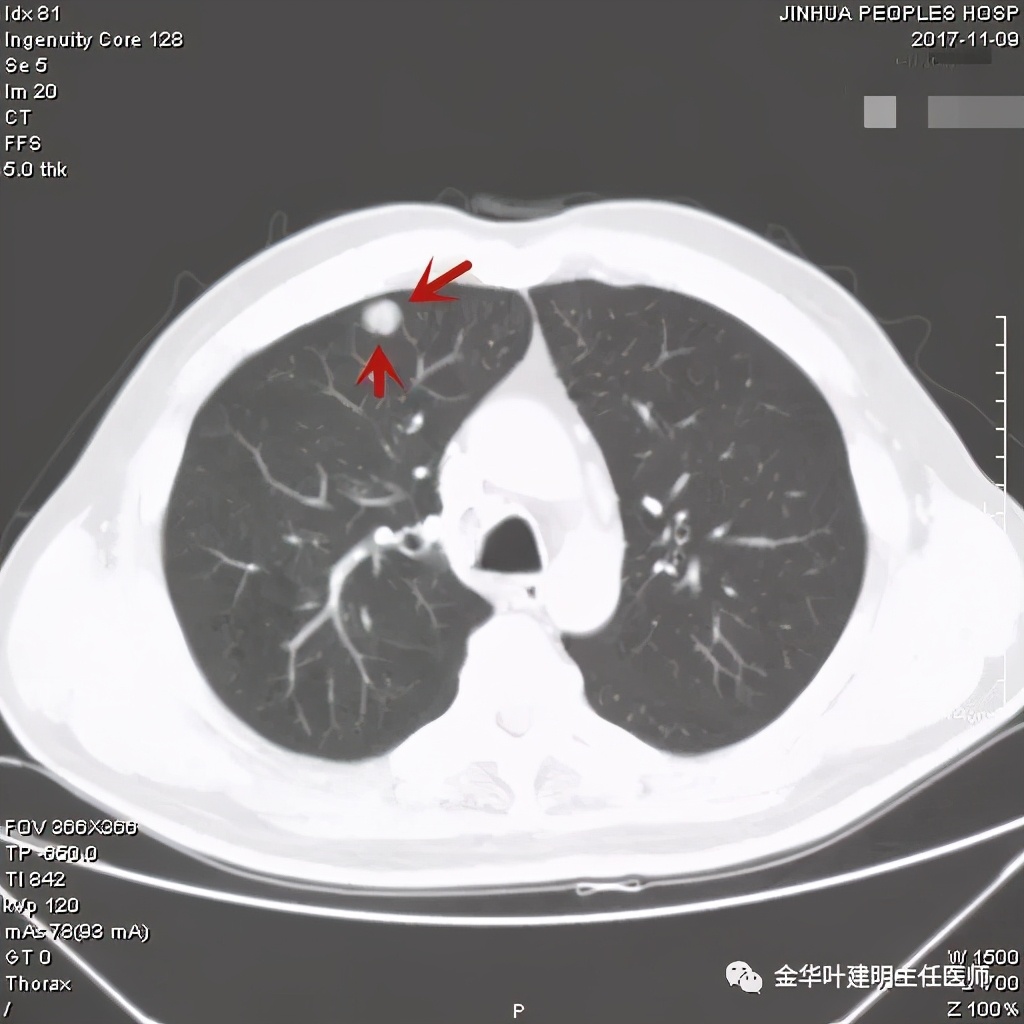

病灶在上图层面似见支气管也是贴壁的。那么增强后又是如何呢?

上图示病灶边缘过于光滑(绿色);局部有点状钙化(蓝色)

上图示病灶边缘过于光滑(绿色);血管贴边(桔色);

上图示病灶边缘过于光滑(绿色);血管贴边走行(桔色)

以上几图也示病灶边缘过光(绿色);血管贴边,感觉没受侵犯(桔色)

事前来看,达2.4厘米的不均质实性肿块,增强有轻度不均匀强化,血管贴边走行,支气管疑有截断,恶性不能除外,而且可能性较大。但现在经过手术已已经证实是错构瘤的情况下,我们回头来看,其实有许多不符合恶性的地方:

1、病灶的每个层面,边缘都过于光滑了。肺癌一般到这个大小总要有棘突、分叶、毛刺、牵拉周围胸膜等边缘异常的征象;

2、肿瘤大于2厘米以上,又紧贴血管,多有血管走行异常、受侵或血管进入等征象;

3、支气管截断不确切,若术前能三维重建或支气管镜检查可能能明确是否有支气管受累;而且占位致支气管截断,容易有刺激性咳嗽症状;

4、轻度强化是否可靠?肿瘤达2.4厘米,是否强化会比较明显,因为血供要求较多呀。